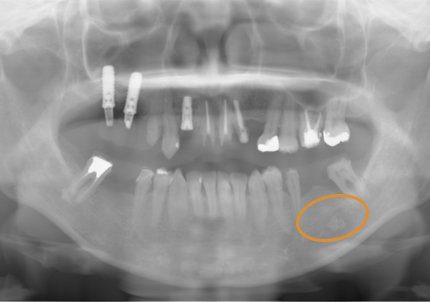

11.経過レントゲン

↑2006年4月24日

↑2008年12月